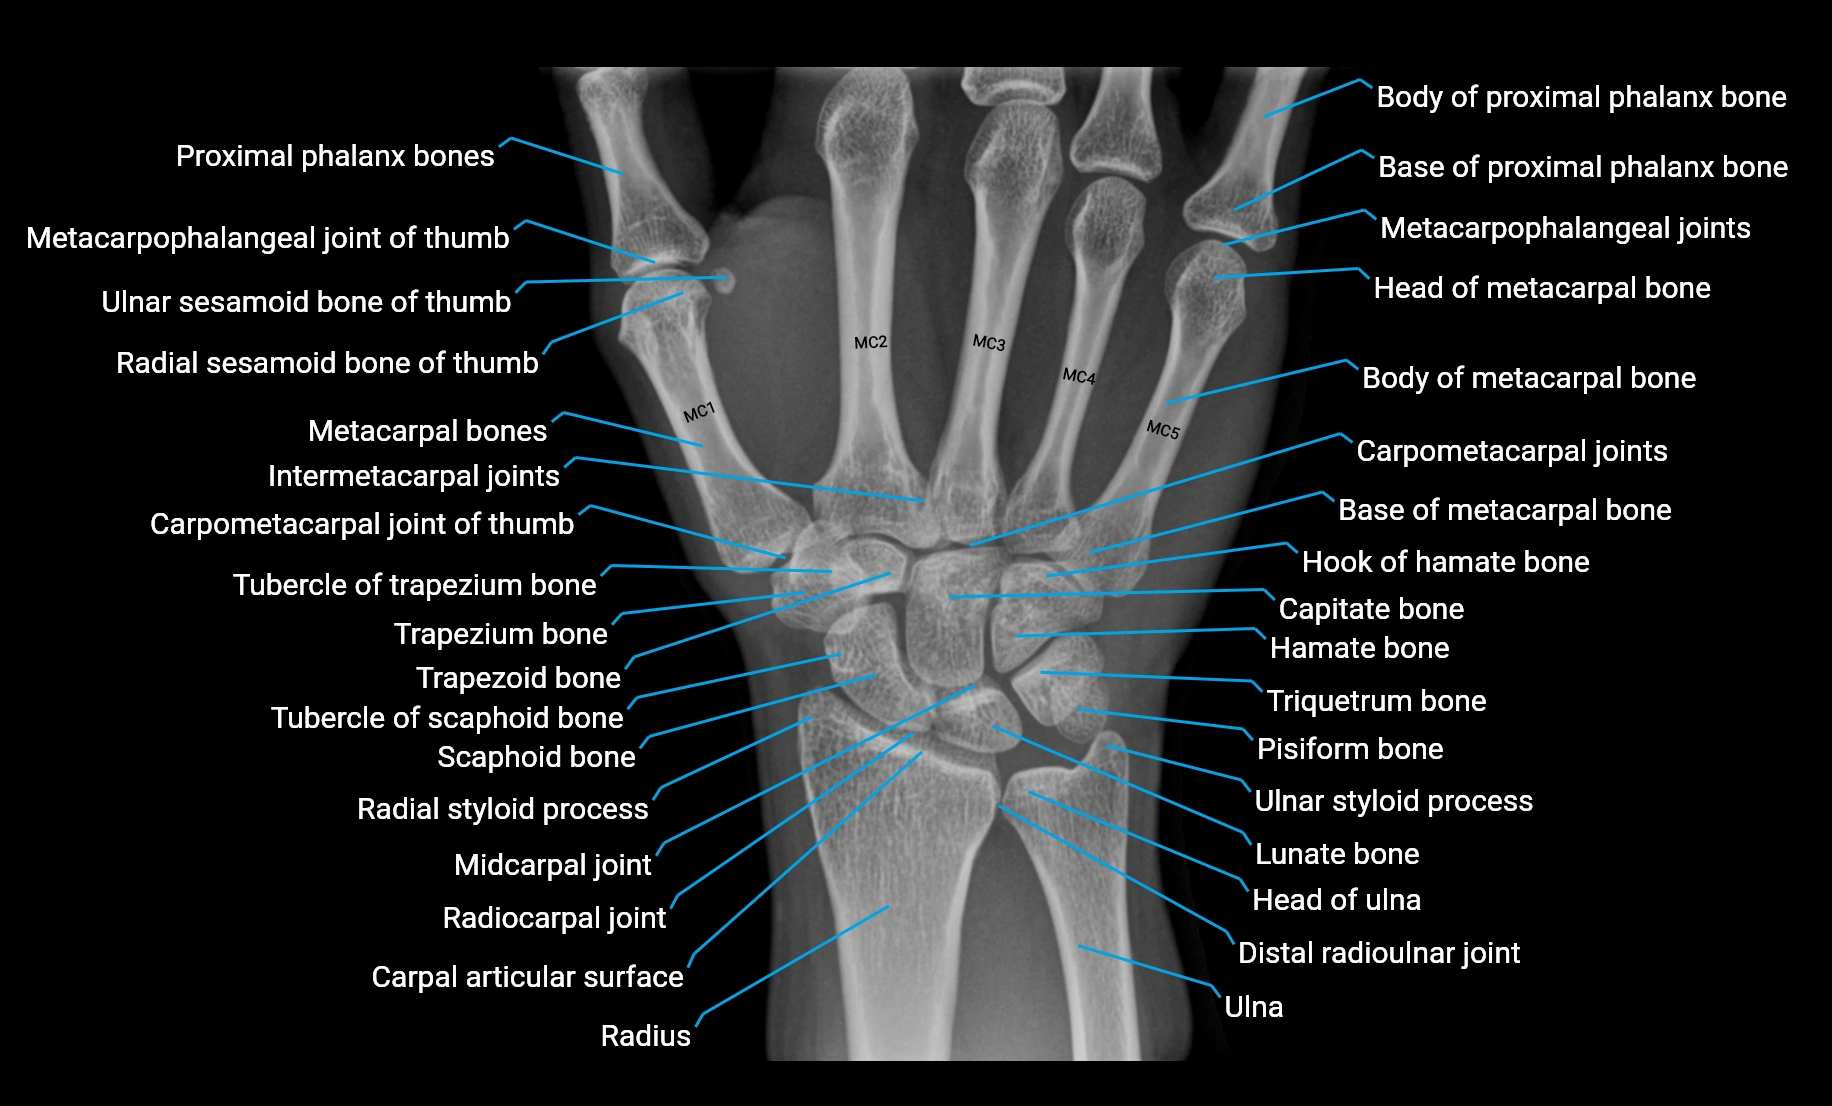

CT Appearance

Non-Contrast CT:

• Muscle: soft-tissue density, well defined in the hypothenar region.

• Tendon: linear low-density structure extending to the base of the little finger.

• Calcification or chronic scarring may appear as localized high-density foci.

• Useful for assessing bony attachment sites at the pisiform and proximal phalanx.